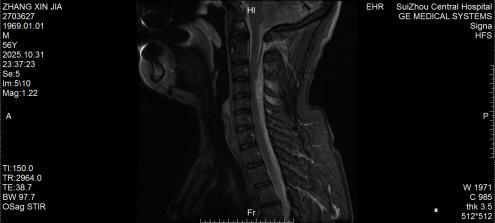

圖2:術(shù)后MRI見脊髓壓迫解除

3.治療原則:一旦確診,72小時(shí)內(nèi)是手術(shù)黃金期,核心是清除血腫、解除神經(jīng)壓迫。隨州市中心醫(yī)院采用的急診減壓手術(shù),能最大程度挽救神經(jīng)功能,這也是5例患者均無后遺癥的關(guān)鍵;

隨州市中心醫(yī)院脊柱外科團(tuán)隊(duì)強(qiáng)調(diào),自發(fā)性椎管內(nèi)出血雖兇險(xiǎn),但并非不可治。今年救治的5例患者,均因就診及時(shí)、手術(shù)規(guī)范,最終全部康復(fù)出院。